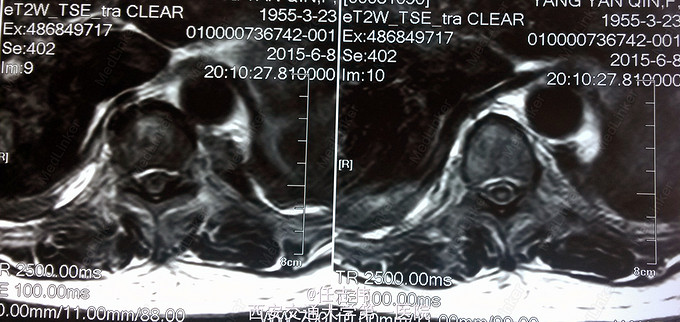

患者女性,60岁,车祸伤致双下肢感觉活动不能8h入院。 8小时前坐农用车时,被横杆撞倒腰部,摔下后感觉胸背部疼痛,双下肢活动不能,伴有短暂昏迷病史。遂来我院就诊。

左侧胸壁广泛压痛,呼吸急促。专科查体:胸背部广泛压痛,自腹股沟平面以下感觉、运动消失,腹壁反射消失,肛门反射消失,巴氏征阴性。双上肢感觉运动正常,骨盆分离挤压试验阴性。

诊断:1.胸11椎体骨折伴截瘫(Frankel A级)2.闭合性胸部损伤,肺挫伤,多发肋骨骨折,双侧胸腔积液 处理:1.急诊入院告病危,心电血氧监护;2.予以甲强龙冲击治疗;3.次日复查胸部CT,查看肺部损伤情况及胸腔积液,后予以右侧放置闭式引流。患者氧合不稳定,2日后复查胸片胸腔积液减少,予以行后路减压内固定融合术。 手术:术中见局部软组织损伤严重,胸11-12棘上、棘间韧带断裂,胸10、11、12双侧关节突有骨折移位,胸11椎板骨折,胸11左侧不能置入椎弓根螺钉,遂行单纯固定。脊髓局部挫伤明显,并有硬膜破损,予以处理。